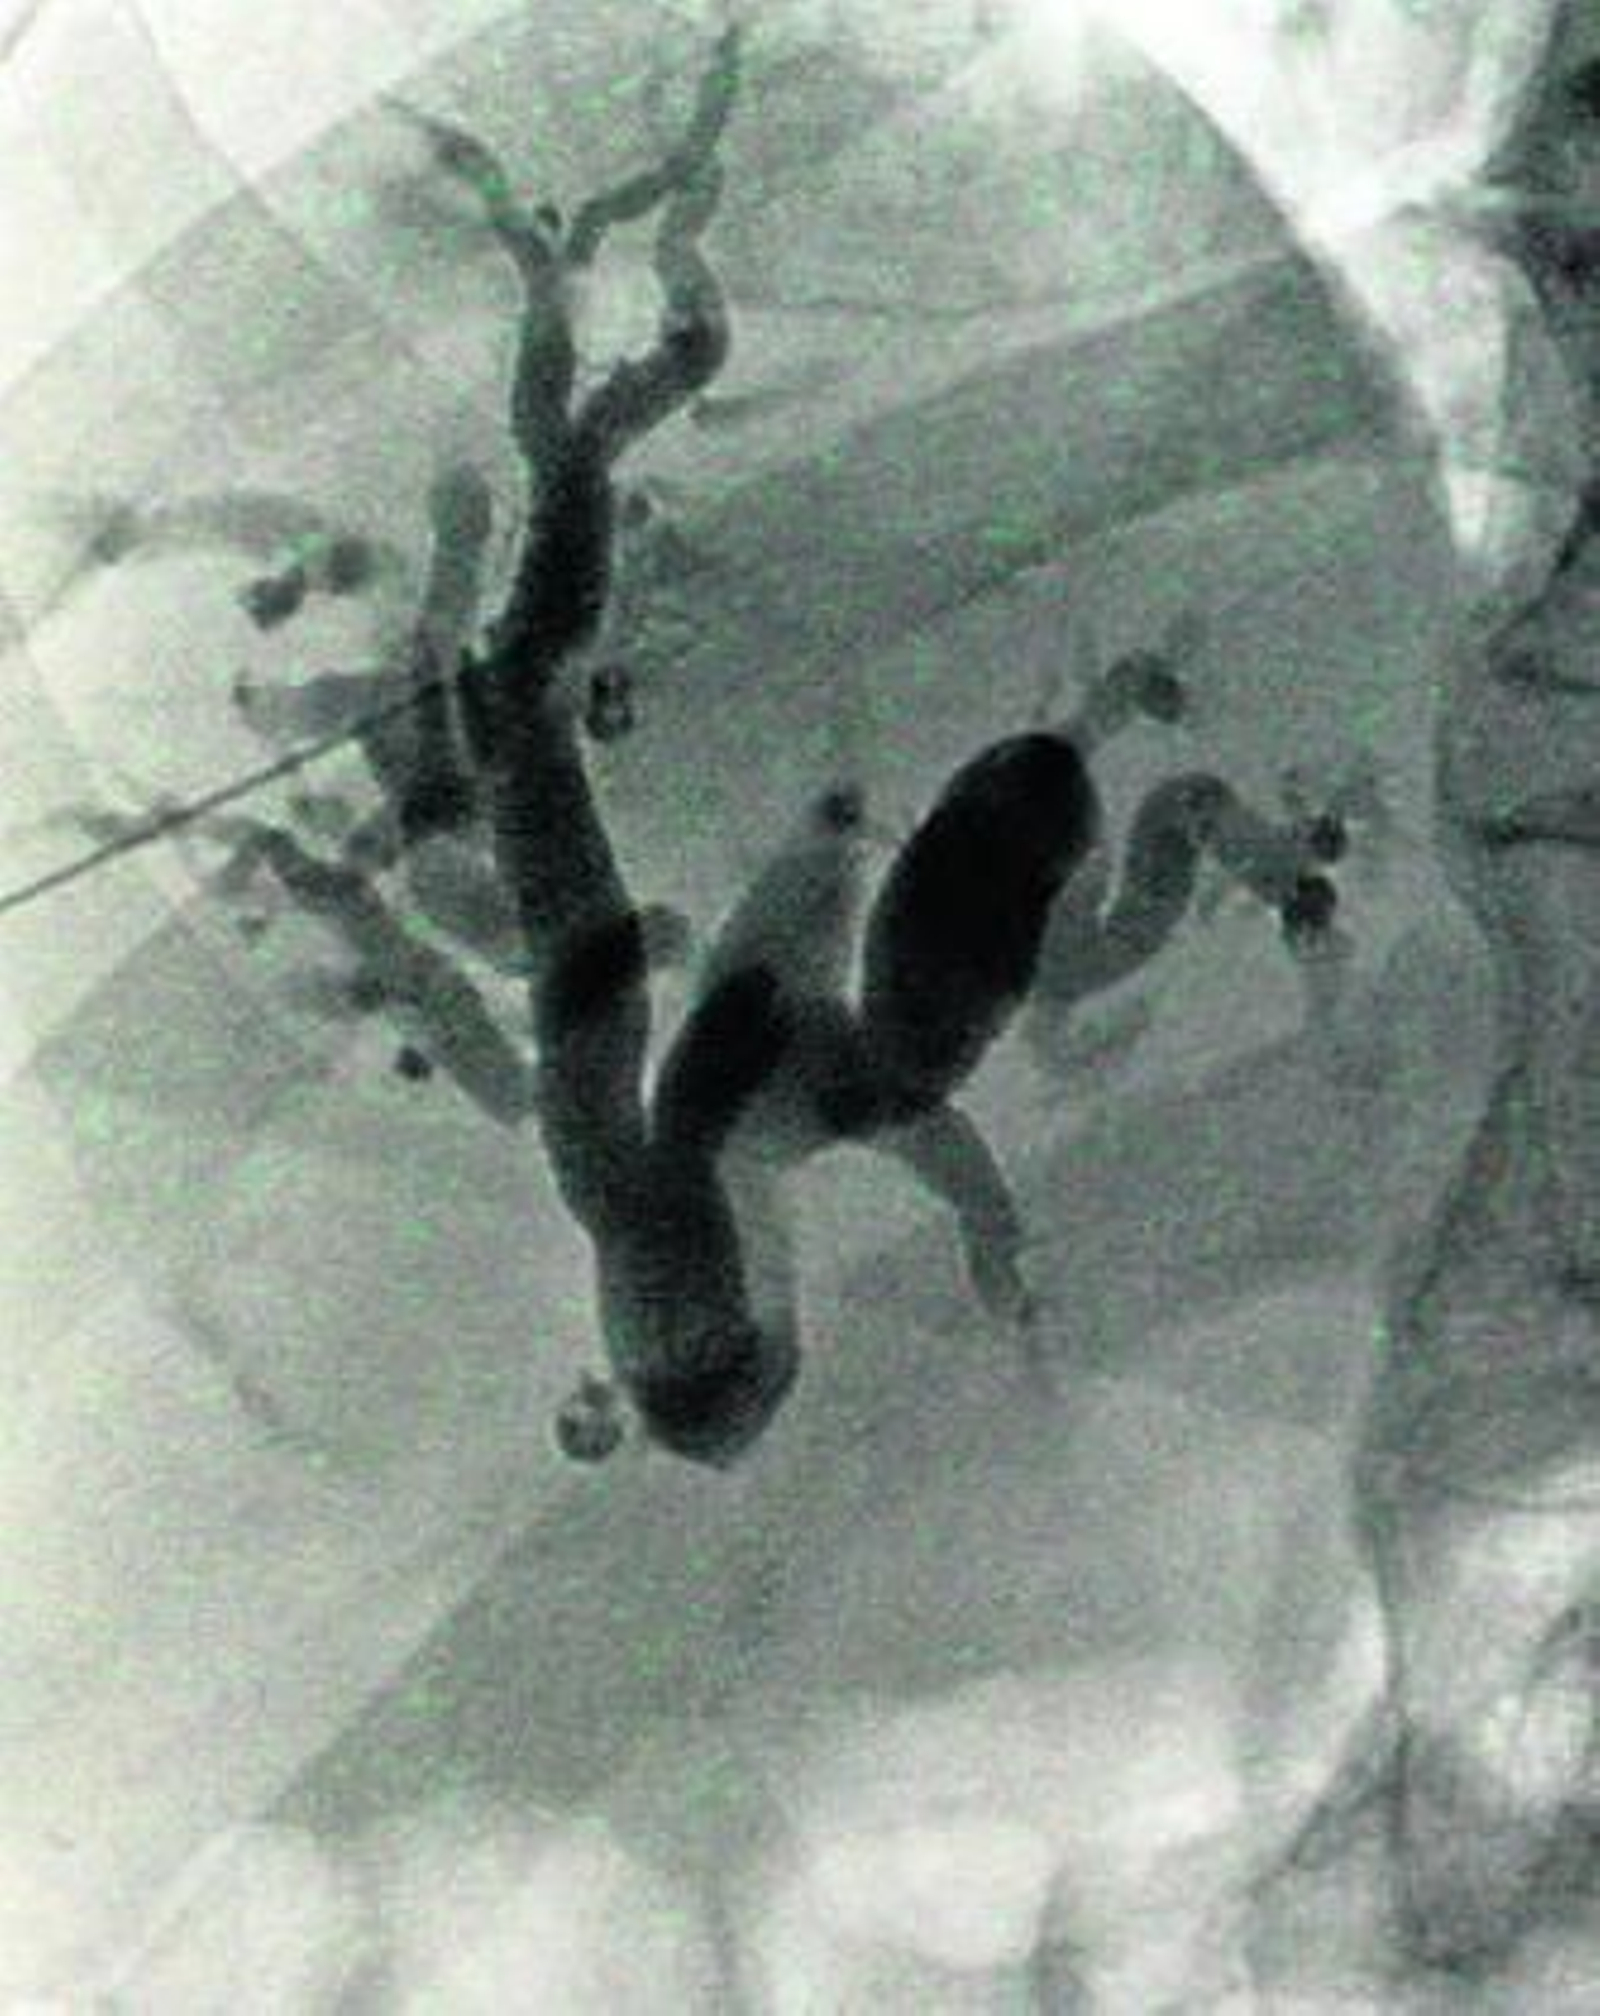

Se trata de intervenciones poco invasivas que, en lenguaje coloquial, permiten desatascar todos los conductos que atraviesan nuestro organismo. Así se ha usado para obstrucciones de orina, sangre o bilis pero lo que llama más la atención es su empleo en algunos cánceres.

Los procedimientos se realizan con control de imagen de la zona en cuestión, que se obtienen a través de imagen radiológica normal, TAC o ecografía. A través de pequeñas punciones en la piel se entra en los vasos sanguíneos, normalmente por la arteria femoral. Desde ahí se llega a las arterias que llevan sangre, con alimento y oxígeno, al tumor y es ahí donde se liberan unas pequeñas partículas cargadas de quimioterapia. Así se consigue bloquear la llegada de sangre y con ello el crecimiento del tumor y destruirlo. Además se logra liberar el medicamento justo donde se encuentra el tumor. Por otro lado, mediante la punción de una vena, se instala un reservorio -pequeño dispositivo situado bajo la piel- que lleva la dosis de quimio hasta venas donde el flujo de sangre es más intenso. Se evita de esta manera lesionar las venas de los brazos y permite administrar el tratamiento de forma ambulatoria, lo que supone una mayor comodidad para el paciente.

La actividad de Radiología Vascular e Intervencionista lleva la misma filosofía que la de Hemodinámica, si bien en el primero de los casos, se extiende a otros ámbitos. Como en Hemodinámica, el proceso es desbloquear el conducto afectado -a veces son los propios tumores los que oprimen conductos o vasos- e instalar un stent que garantice el normal funcionamiento, normalizando así el paso de la sangre, bilis u orina. Una de las ventajas que tiene este tipo de intervenciones es que son poco agresivas y no necesitan prácticamente ingreso hospitalario. Aunque el equipamiento, muy ligado a los avances tecnológicos, supone un desembolso considerable éste se amortiza por ese menor nivel de hospitalización y por otras variables como la aparición de menos complicaciones y la posibilidad de llevar a cabo tratamiento ambulatorios.